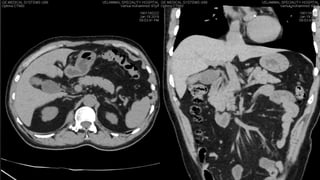

Hepatobiliary tumor board (1)

• 16.

ITT population SOR+SIRT (n=216) SOR (n=208) Median OS,months (95% CI) 12.1 (10.6, 14.6) 11.5 (9.8, 13.8) HR 1.0067 (0.82,1.25) p=0.951 Conclusions: • Addition of SIRT to SOR did not result in a significant improvement in OS vs. SOR alone • Subgroup analyses (hypothesis generating) suggest a potential clinical benefit for younger patients, and patients presenting with non-alcoholic aetiology, or without cirrhosis OS in the PP population (N=288) PP population subgroup analysis* SOR+SIRT vs. SOR HR p-value ≤65 years 0.65 0.05 Non-alcoholic aetiology 0.63 0.012 Without cirrhosis 0.46 0.02 0 0.0 0.4 0.6 0.8 1.0 12 Months Survivalprobability 62 0.2 Number at risk: 24 20 36 5 48 1 60 0114 75 23 8 2 0174 SOR+SIRT SOR Censored PP population SOR+SIRT (n=114) SOR (n=174) Median OS, months (95% CI) 14.07 (10.9, 16.4) 11.14 (9.7, 13.9) HR 0.86 (0.67,1.11) p=0.253